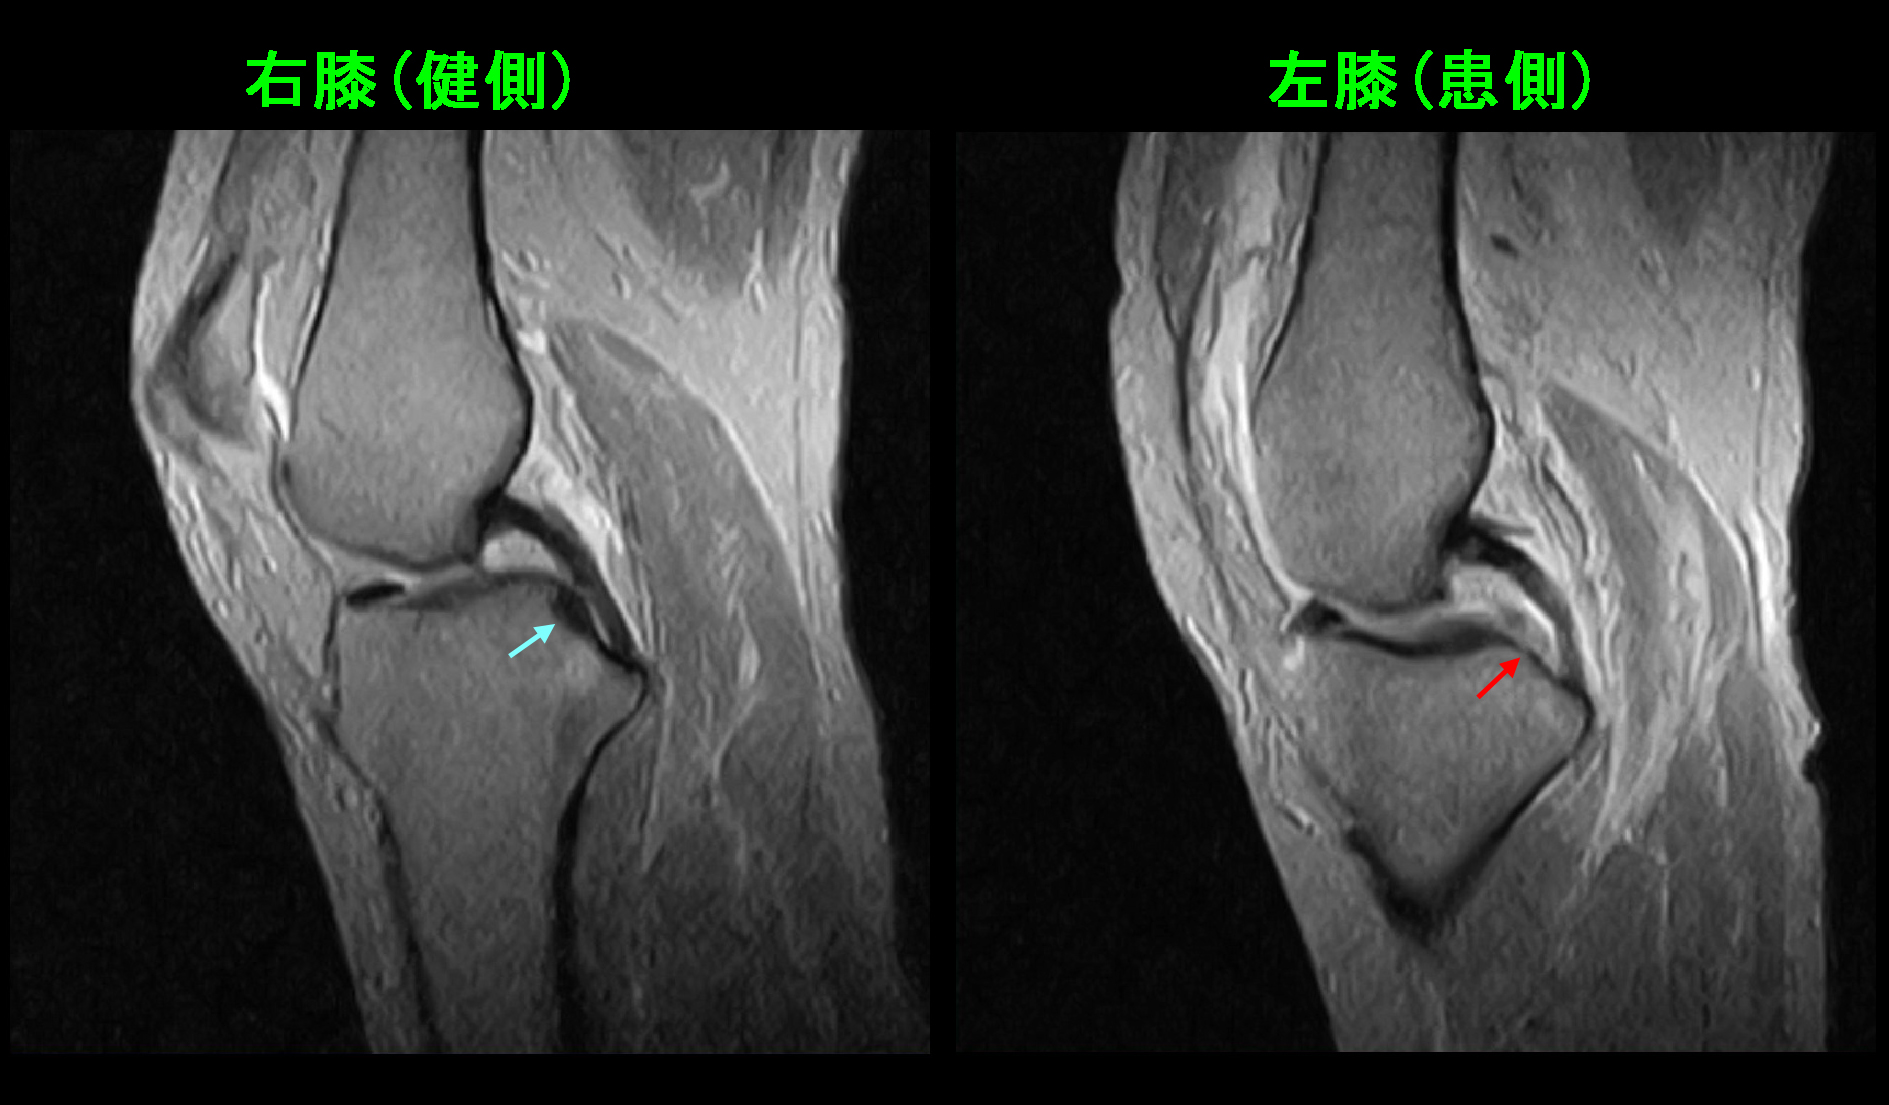

66才女 MR1.jpg

GR冠状断(前後像)です。左膝赤矢印が内側半月板の後根部となりますが、健側右膝は内側半月板は黒く描出されていますが、左膝後根部は白くなっており、損傷(=変性)して出血しているようなイメージです。内側半月板の内側縁よりも白くなっており(オレンジ矢印)、損傷していることが分かります。

66才女 MR2.jpg

GR矢状断(横から見た画像)です。健側右膝では青矢印の内側半月板は中央で黒くしっかりと脛骨に付着しています。しかし、左膝の内側半月板後根部は白くなっており、脛骨から剥がれそうな状態です。左膝へのヒアルロン酸の関節内注射を週1回、連続5回行つとともに服薬で治療しました。ヒアルロン酸の関節注射は5回施行後は2週に1回で継続しています。同年の9月2日まで2か月半加療して、症状は軽減傾向があって通院は終了しています。